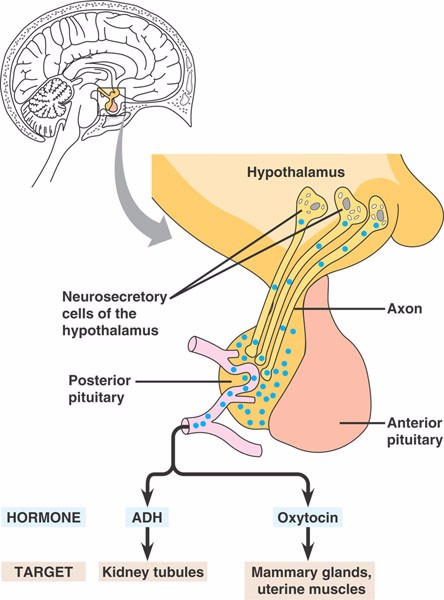

45_07PostPituitaryHormone

neurohypophysis.html